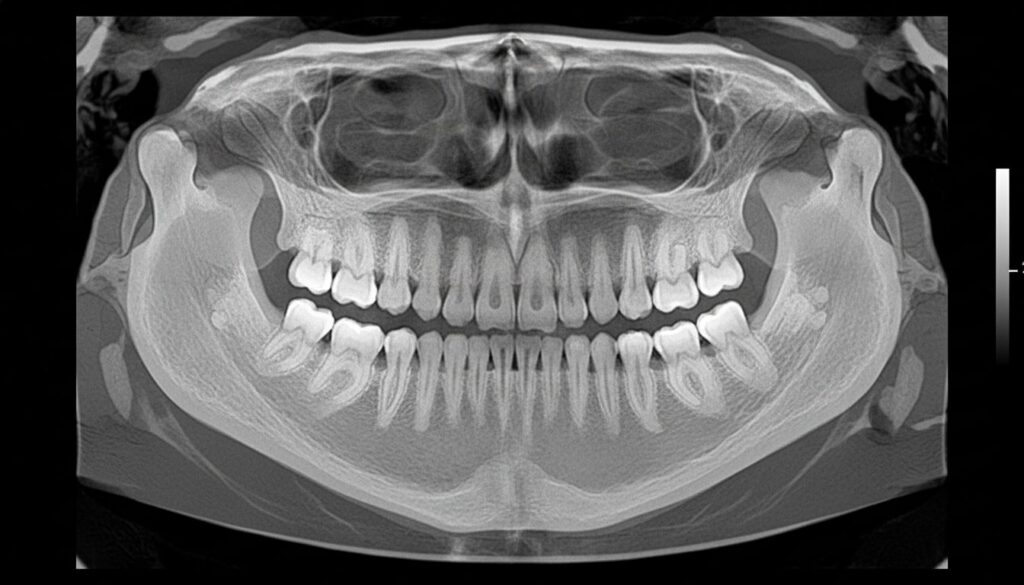

CT診断による骨の量と質の評価

**歯科用CT**は、3D情報で神経・血管位置を把握し、インプラント等のリスク低減に活用されます。

CT撮影によって、骨の高さ、幅、密度などを正確に測定することができます。この情報をもとに、インプラントを安全に埋入できるかどうか、骨造成が必要かどうかを判断します。

初回ではレントゲン撮影・歯周病検査・口腔内写真などを実施し、痛みや欠け等がある場合は応急処置を行います。CT撮影によって、骨の状態を詳細に評価します。